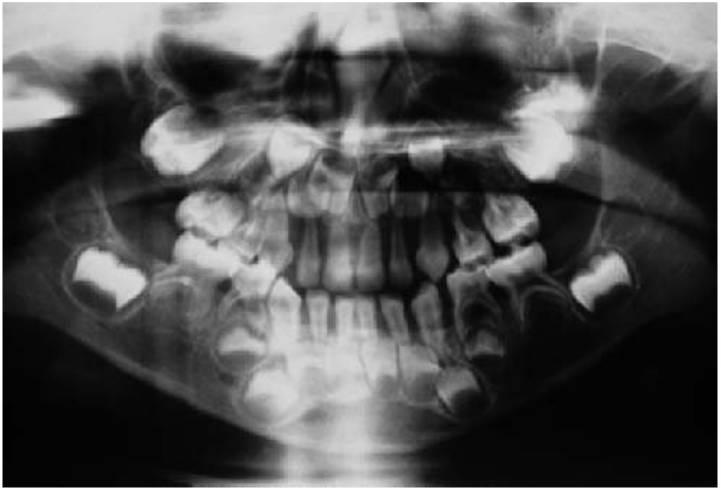

La cardiopatía congénita (CC) presenta una incidencia de 8-10 casos por 1.000 nacidos vivos y constituye el mayor grupo en enfermedades cardiovasculares pediátricas. Aunque la mayor parte de las lesiones se dan a nivel individual, varias constituyen componentes de síndromes o trastornos cromosómicos, como el síndrome de Down (trisomía 21) (fig. 10. 2A) y el síndrome de Turner (cromosoma XO), en el que más del 40% de los niños que los padecen se ven afectados por CC. Sin embargo, en la mayoría de los casos, no puede determinarse una causa concreta y se asume una etiología multifactorial. Entre los factores de riesgo conocidos asociados a CC se cuentan rubéola materna, diabetes, alcoholismo, irradiación y fármacos como talidomida, fenitoína sódica y warfarina sódica.

Todos los trastornos cianóticos presentan derivación de derecha a izquierda de sangre desaturada. Los defectos cianóticos se hacen clínicamente evidentes cuando 50 g/l de hemoglobina desaturada están presentes en la sangre arterial periférica. Los lactantes con cianosis leve pueden mantener una coloración rosada en reposo, pero adquieren una tonalidad azul intensa al llorar o hacer ejercicio. Los niños con defectos cianóticos presentan un importante riesgo de desaturación durante la anestesia general, por lo que la consulta con el cardiólogo y el anestesista pediátricos resulta esencial (fig. 10.2).